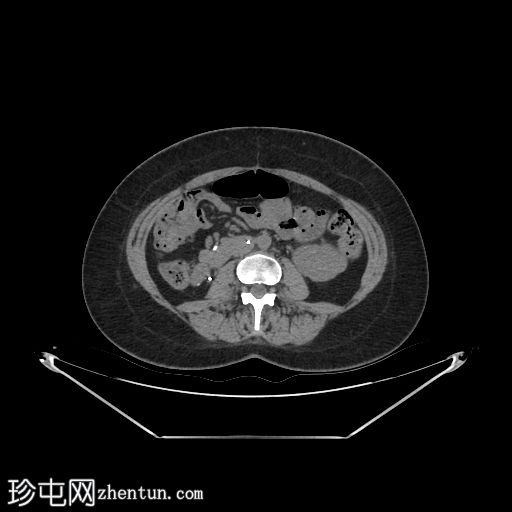

轴位

平扫

自体肾脏和胰腺(胰头、胰体和胰尾)明显萎缩。

本例中,影像学检查显示原位肾脏和胰腺明显萎缩,符合长期糖尿病合并慢性肾脏病的表现。肾移植位于左髂窝,与同侧髂血管的动脉和静脉吻合通畅,肾实质均匀强化,这些影像学表现均符合功能性肾移植的影像学特征。移植胰腺位于右侧腹膜后,形态和位置均符合原位胰腺,供体十二指肠袢与原位十二指肠吻合良好。